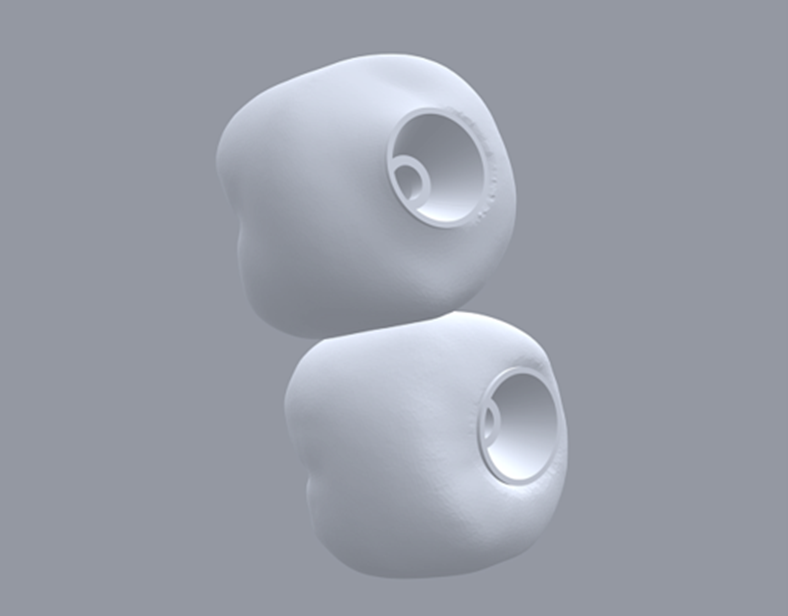

Selecionamos um caso clínico para ilustrar o fluxo de trabalho digital para Mini Cônico, onde foram planejadas duas coroas unidas nos elementos dentários 36 e 37 em zircônia monolítica, feitas sobre o pilar para próteses múltiplas.

Neste caso, a prótese múltipla foi desenhada sobre o Mini Cônico e as duas coroas foram fresadas unidas. Após a maquiagem final da zircônia monolítica, as coroas foram parafusadas sobre o Mini Cônico com um torque de 10 Ncm.

Podemos acompanhar o passo a passo das etapas, desde a seleção da altura do transmucoso do Mini Cônico até a instalação das coroas unidas no fluxo totalmente digital sem a utilização de componentes metálicos.